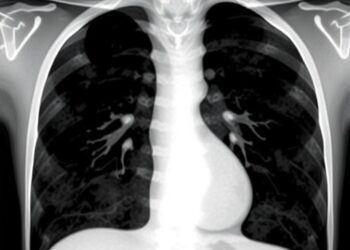

New Grading System Proposed for Invasive Lung Squamous Cell Carcinoma in Journal of Thoracic Oncology Study

Invasive lung squamous cell carcinoma (LUSC) represents a formidable challenge within thoracic oncology, accounting for roughly twenty-five percent of all ...